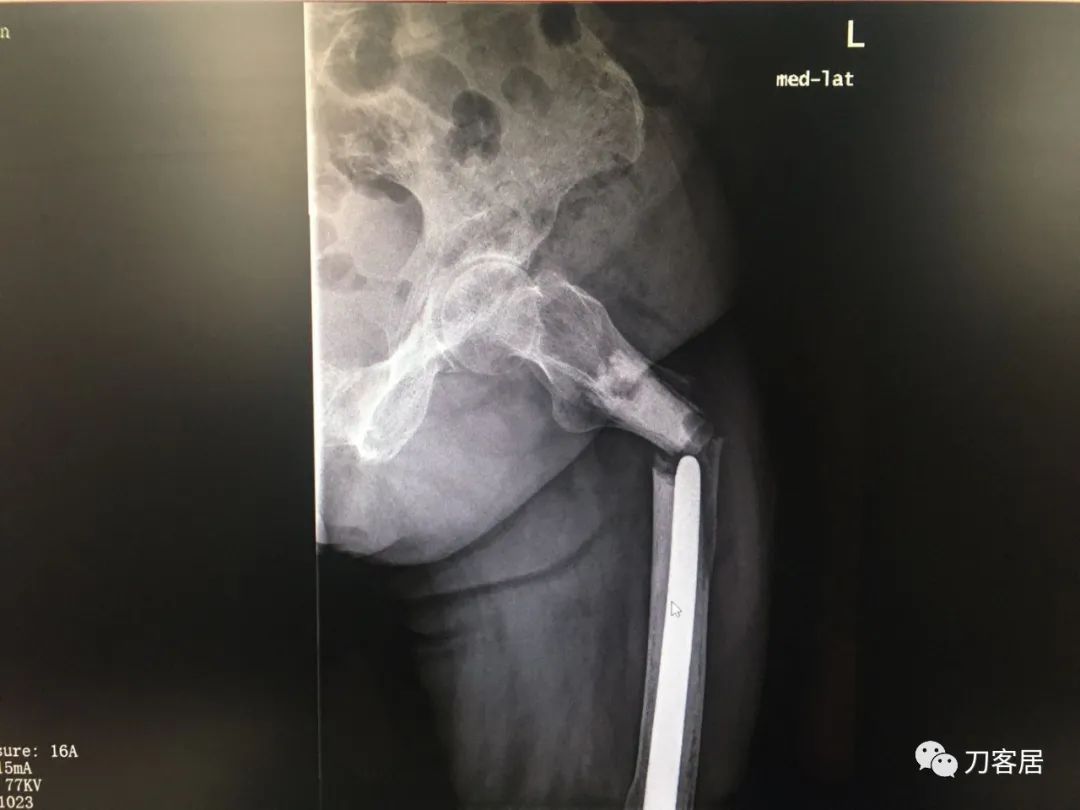

我不是中医黑2: 股骨髁上骨折,中药外敷治疗致股骨髁上陈旧骨折,县级中医医院手术,骨折病例用了骨肿瘤手术关节置换假体。

摘要: 这个病例第一次是摔伤致股骨髁上骨折,不知何种原因患者家属要求保守治疗,外包中药处理后骨折未愈合骨不连,后到一个县级中医院行了关节置换,选择的是肿瘤型假体。

现术后2年摔倒后致假体周围骨折。病人错误的选择,医生错误的治疗,最后导致不好的结局。

风吹麦浪10:25AM分享个病例,女性,67岁,外院手术后2年,现假体周围骨折。

风吹麦浪10:45AM这个病例第一次是摔伤致股骨髁上骨折,后不知何种原因家属要求保守治疗包中药处理后骨折未愈合骨不连,后到一个县级中医院行了关节置换,选择的是肿瘤型假体。

现术后2年摔倒后致假体周围骨折。

何川2:58PM我是坚决反对这种病例一期做置换。如果,实在要做假体,要做好精细严密的术前计划,这是骨折病例,不是肿瘤,那些碎掉的骨块完全可以利用起来,延长杆就不需要用很长了。

从X片看没有涉及副韧带止点,可以保留重要骨块,加内固定钢板辅助,非限制性假体即可,实际用了铰链、这么长的杆,全髓腔骨水泥,基本打定主意一锤子买卖,把自己后路全断了。

刘忠堂,长海关节3:01PM@上海瑞金医院何川这个陈旧性骨折内固定是最好的选择,尤其是对基层医生。